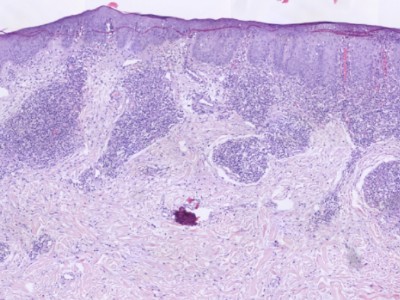

PA:Infiltraat rond de haarfollikels (folliculotropism)

zonder spongiose, met atypische CD4+ T-lymfocyten. Vaak folliculaire mucinosis.

Andere kenmerken kunnen zijn verwijd infundibulum, perivasculaire en periadnexale

dermale infiltraten, Langerhans cellen, eosinofielen en plasmacellen, infiltraten

rond zweetklieren (syringotropisme). Weinig of geen epidermotropism. De lymfocyten

kunnen klein zijn, gemiddeld, of groot blastocytair. Soms CD30+.

![Histologie folliculotrope mycosis fungoides (click on photo to enlarge) [source: Kevin Kwee / Afdeling Pathologie MUMC] Histologie folliculotrope mycosis fungoides](../../../pacoupes/thumbnails/folliculotrope-mycosis-fungoides-1.jpg) |

![Histologie folliculotrope mycosis fungoides (click on photo to enlarge) [source: Kevin Kwee / Afdeling Pathologie MUMC] Histologie folliculotrope mycosis fungoides](../../../pacoupes/thumbnails/folliculotrope-mycosis-fungoides-2.jpg) |

ingescande coupe (zoom) |